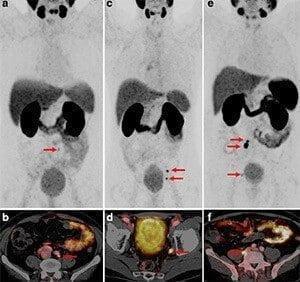

Ga-68 PSMA PET/CT is a new generation application used in the diagnosis and treatment of prostate cancer. It is used for diagnosis